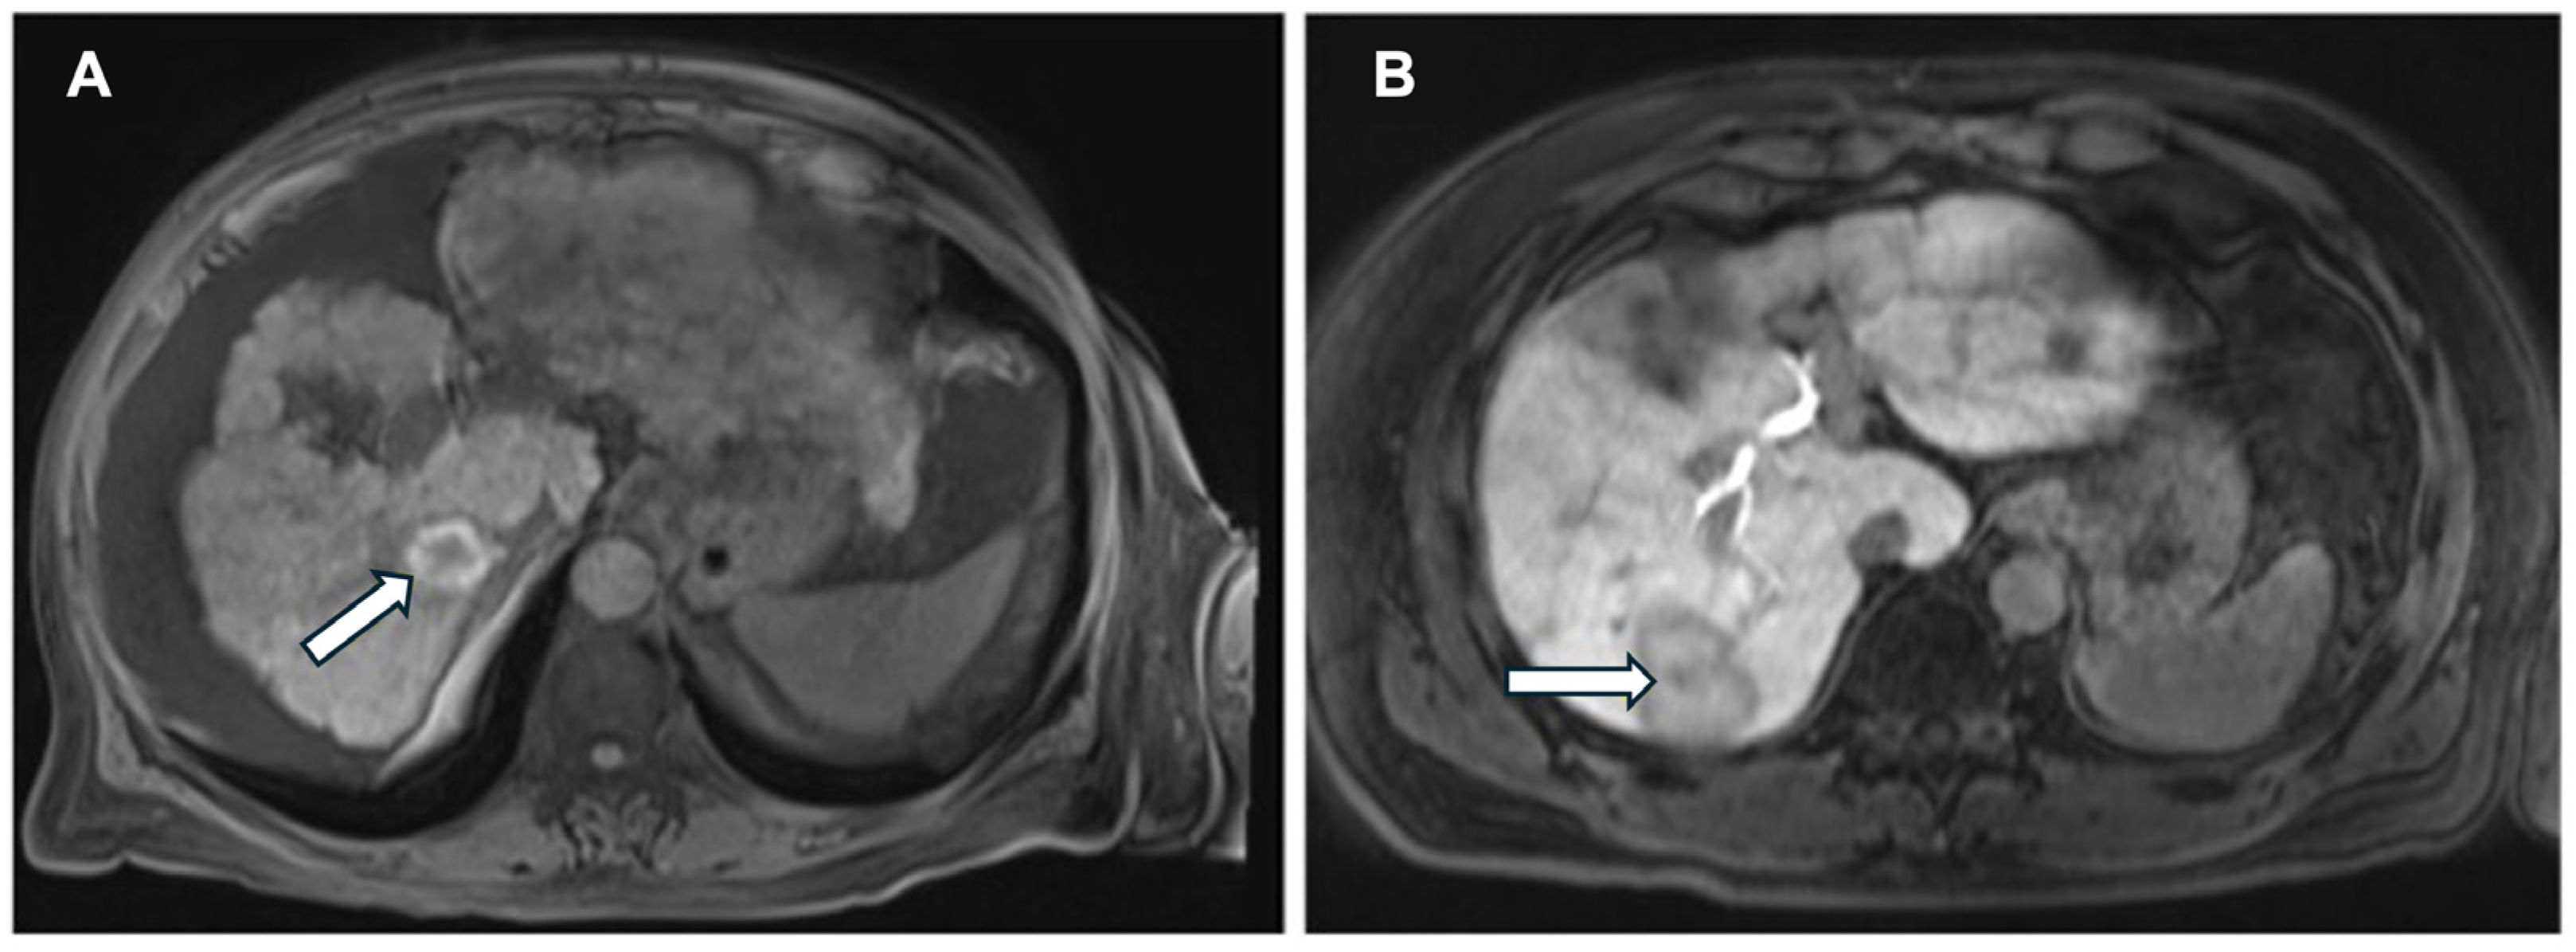

- Zhu, Y.; Feng, B.; Wang, P.; Wang, B.; Cai, W.; Wang, S.; Meng, X.; Wang, S.; Zhao, X.; Ma, X. Bi-regional dynamic contrast-enhanced MRI for prediction of microvascular invasion in solitary BCLC stage A hepatocellular carcinoma. Insights Imaging 2024, 15, 149. [Google Scholar] [CrossRef]